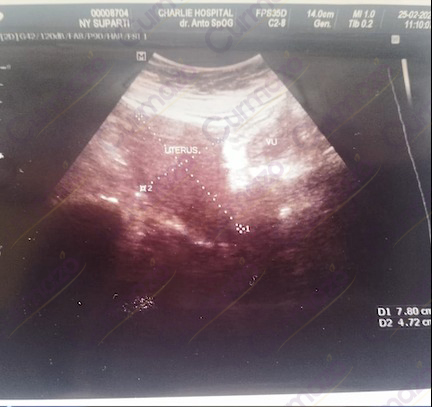

Oktober 2022, saya rasakan sakit perut, kesulitan buang air besar, nyeri pinggul, perut kembung, dan detak jantung yang tidak teratur. Hal ini membuat hari-hari saya dipenuhi dengan penderitaan.

Akhirnya saya periksa ke dokter dan ternyata ada kista berukuran 4,7 x 4,1 cm.

Tidak pernah menjalani tindakan apapun sebelumnya, saya hanya mengandalkan obat dokter untuk meredakan gejala. Namun, efeknya hanya bersifat sementara, dan kista tetap menjadi hal yang tidak menyenangkan dalam hidup saya.

Setelah Konsumsi Herbal

Agustus 2023, setelah berbagai pertimbangan, saya memutuskan untuk mencoba solusi herbal. Saya menemukan di google herbal Curmazo dan K-Muricata. Setelah konsultasi dan melihat sudah banyak yang berhasil, saya memesan untuk 1 bulan pengobatan.

5 Hari pengobatan sakit pada perut mulai berkurang. Namun nyeri pada pinggul masih terasa dan bab masih sulit.

21 hari pengobatan perkembangan yang semakin signifikan saya rasakan, bab sudah mulai lancar dan tubuh menjadi sangat bugar. Saya semakin semangat melanjutkan herbalnya dan memesan untuk paket 1 bulan lagi.

Bulan ke-2 Alhamdulillah Nyeri pinggul dan perut kembung yang selalu mengganggu juga menghilang. Bahkan, detak jantung saya yang sebelumnya tidak teratur kini telah kembali normal.

Bulan ke-3, Saya cek ke dokter lagi. Hasilnya sangat mengejutkan, kista berukuran 4,7 x 4,1 c,m hilang total.

Kini kehidupan saya kembali normal, saya bisa beraktivitas sebagaimana layaknya ibu rumah tangga lainya, dapat melayani suami dan mengurus anak-anak dengan baik .